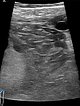

Pre-pregnancy ultrasound imaging with 10.4 MHz linear transducer. Evidence of an intramuscular subfascial venous malformation with multiple hypoechoic venous channels.

In the 21st week of gestation clear enlargement of the venous malformation on ultrasound with 10.4 MHz linear transducer. Progression of the intramuscular subfascial venous malformation with multiple hypoechoic venous channels. Partly echogenic areas due to clot formation can also be seen now inside the lesion.